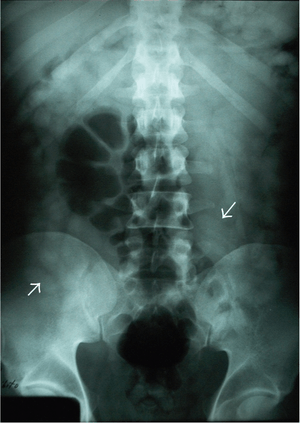

Free intra-abdominal air below the diaphragm. Body-packing with multiple foreign bodies ("balls" of hashish).

Body-packing with multiple foreign bodies ("balls" of hashish).